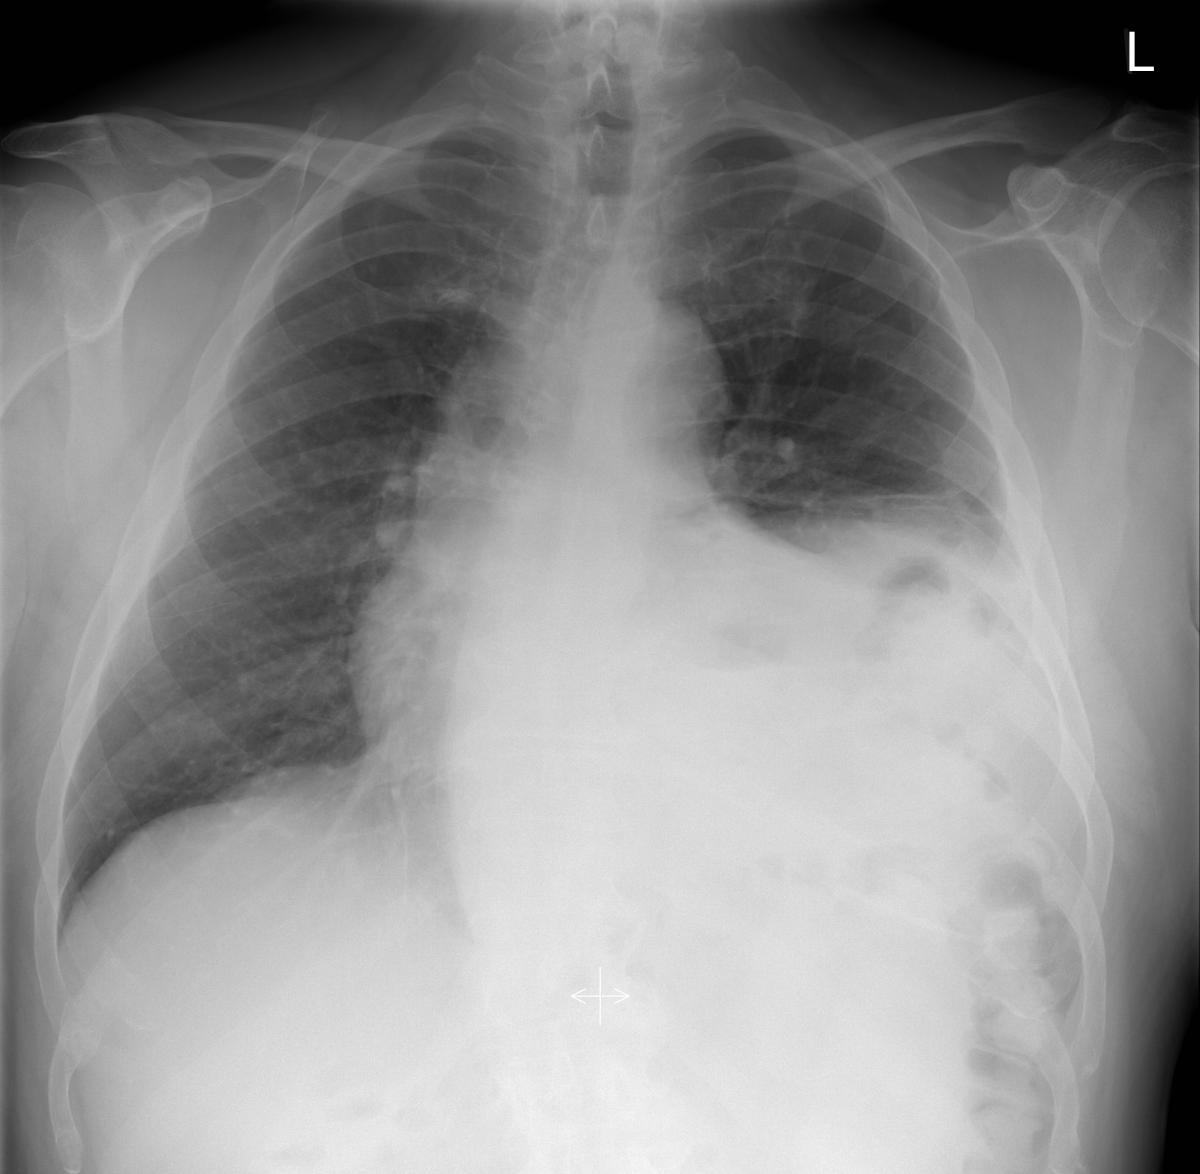

| Figure 1: Pre-operative CXR of the patient shows a left-sided paralyzed diaphragm. |